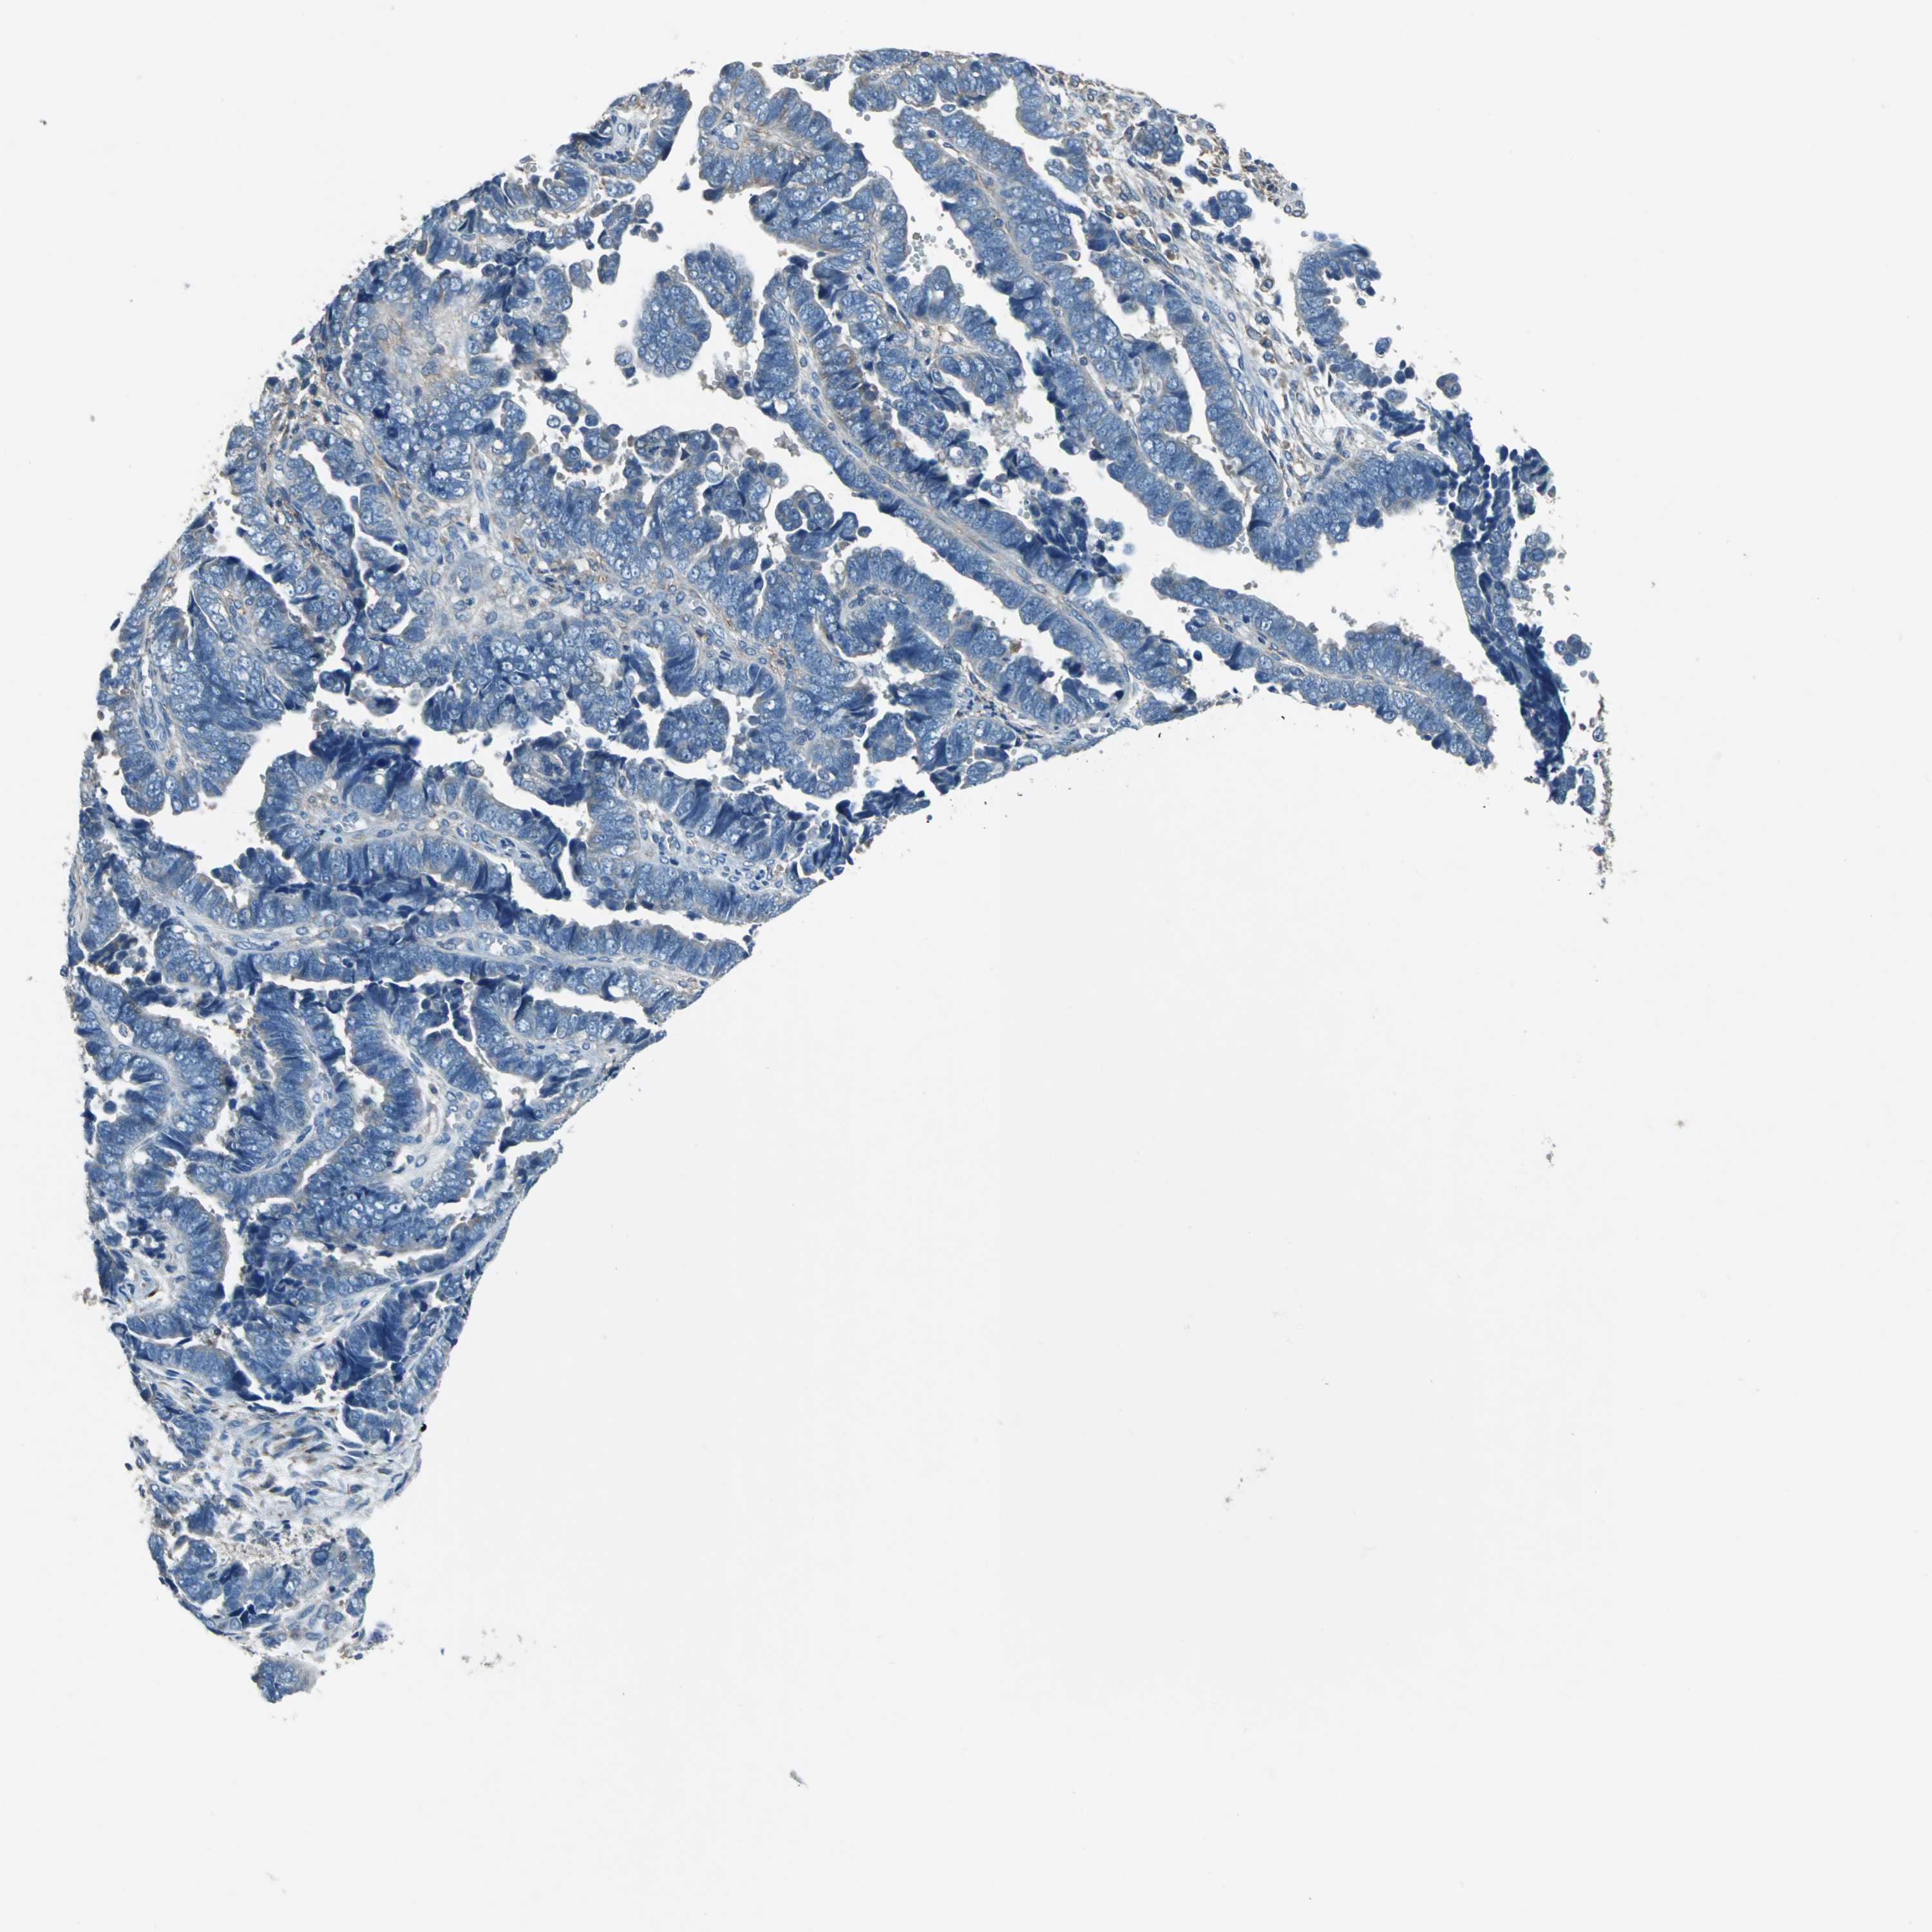

ENDOMETRIAL CANCER - Protein expressioni

A mouse-over function shows sample information and annotation data. Click on an image to view it in a full screen mode. Samples can be filtered based on level of antibody staining by selecting one or several of the following categories: high, medium, low and not detected. The assay and annotation is described here.

Note that samples used for immunohistochemistry by the Human Protein Atlas do not correspond to samples in the TCGA dataset.

Antibody stainingi

Antibody staining in the annotated cell types in the current human tissue is reported as not detected, low, medium, or high, based on conventional immunohistochemistry profiling in selected tissues. This score is based on the combination of the staining intensity and fraction of stained cells.

Each image is clickable and will lead to virtual microscopy that enables deeper exploration of all samples and also displays staining intensity scores, fraction scores and subcellular localization as well as patient and tissue information for each sample.

Antibody HPA006563

Antibody HPA006564

Antibody CAB003844

Antibody CAB016290